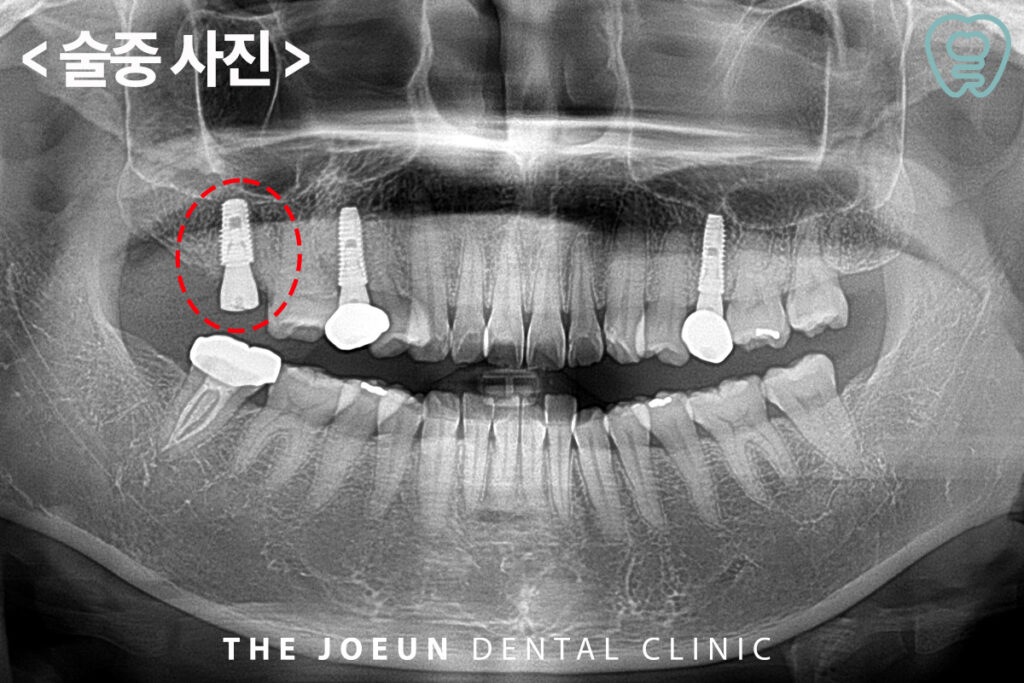

먼저 위쪽 치아를 발치한 후 잇몸뼈가 회복되기까지 기다린 뒤 임플란트 식립을 진행하기로 하였는데요. 그동안에 아래쪽 어금니의 신경치료를 진행하였습니다.

이 치아는 복잡한 C형 근관을 가진 치아였지만 안정적으로 신경치료가 마무리된 모습입니다.

신경치료를 완료한 후 임플란트 식립을 진행하였습니다.